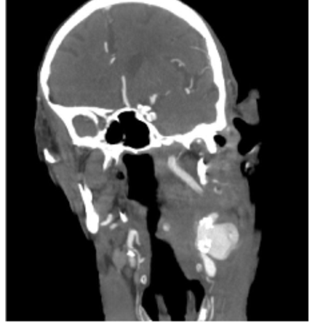

An 88 year-old autonomous but frail male with a history of non-Hodgkin lymphoma and adenocarcinoma of the rectum (T3 N0 M0) under radiotherapy, presented with sudden-onset left cervical pulsatile mass and dysphagia. The patient had no trauma or history of previous surgical intervention on the neck. In the analytical study at admission, the patient had leukocytosis (leukocytes 15.83x103 with 40.7% neutrophils) and a C-reactive protein level of 79 mg/L. The computed tomography angiography (CTA) revealed a left internal carotid artery rupture with a slight deviation of the trachea (Figure 1).

Figure 1 Computed tomography angiography at admission showing a carotid rupture within a calcified atherosclerotic plaque and hematoma compressing the cervical structures (coronal view)